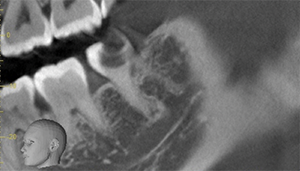

右下の親知らずが疼く症例

- 抜歯前写真(レントゲン)

- 抜去歯の写真(CT画像)

| 年齢 | 30代・女性 |

|---|---|

| 主訴 | 右下親知らずが疼く |

| 親知らずの生え方 | 横向きに生えている |

| 抜歯時間 | 40分 |

| 費用 | 約8,000円(保険診療、CT代含む) |

| 抜歯内容 | 右下の親知らずは横向きに生えて埋まっているため、麻酔をし親知らずの奥に切開を入れて歯ぐきを開き、歯を囲んでいる骨を削り歯の頭部分を割って出してから、残った根の部分を取り出して抜歯は終了しました。 歯ぐきを切った部分は糸で縫っています。このケースでは根の先端が神経に近く麻痺のリスクがありましたが事前にCTを撮影し、神経との位置関係を確認していたため、麻痺が残ることはありませんでした。 約1週間後に糸取りを行い、その際も多少の痛みや腫れはありましたが後日その痛みも無くなりました。 |